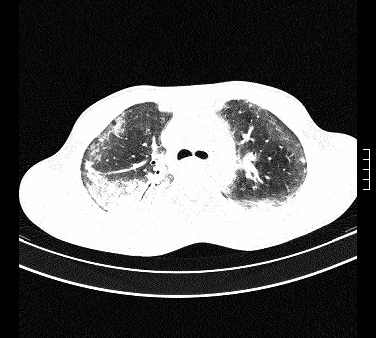

标题: CT15133:M17Y,百草枯中毒患者,典型病例分享 [打印本页]

标题: CT15133:M17Y,百草枯中毒患者,典型病例分享

患者,男,17岁,系我院急诊科收治的一例百草枯中毒患者,做ct检查时,距离服药的时间为3天。上传与大家分享

补充:百草枯进入人体内主要分部于肺和骨骼,肺部损伤24小时内出现水肿,2-3天内出现急性呼吸窘迫综合征,1-2周内出现肺纤维化。(引自陈灏珠,实用内科学12版)

不错,挺好。符合呼吸窘迫综合征